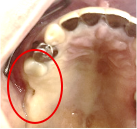

男性 Nさん 70代 (インプラント)

主訴

右下奥の歯が、グラグラして噛むと痛い。

治療内容

歯根の周りの骨が全く無い状態でしたので、保存することができず抜歯しました。3本歯がないところに2本インプラントを埋入しました。

所感

抜歯後、歯がなくなったところを補う方法には、部分入れ歯とインプラントがあります。この症例の場合、右下以外ほとんど歯が残っていますので、もし部分入れ歯にした場合、入れ歯のところで他のところと同じ感覚で噛むことができないので、慣れることが大変です。また部分入れ歯の支えになっている歯に負担がかかりますので、今後さらに歯を失う可能性が大きくなります。インプラントは、自分の歯と同じ感覚で噛むことができ、単独で植立していますので他の歯に負担がかかることがありませんので、更に歯を失うことを防ぎます。

インプラント2本:¥363,000×2本=¥726,000(税込)

ポンティック1本:¥115,500(税込)

合計:¥841,500(税込)

Before

※赤丸を抜歯しました。

After